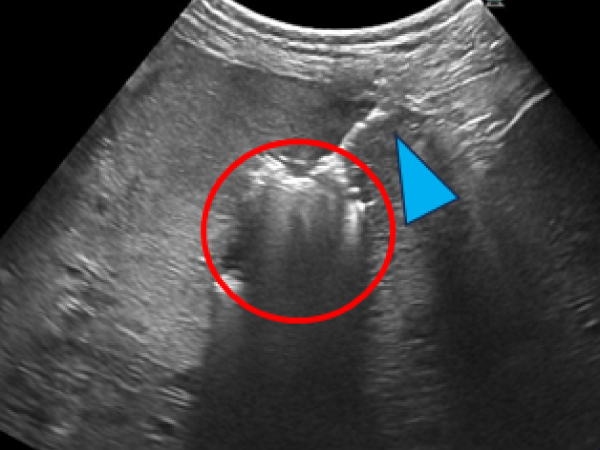

アブレーション実施中の超音波画像

アンテナ(青矢頭)と焼灼されているところ(赤丸)

内側左葉に36.2×45.1㎜の腫瘤が認められ、ツルーカット生検で肝細胞癌と診断されました。 摘出も可能でしたがもともと肝臓が小さく肝機能が低下しているため負担の少なさを考慮してフュージョンイメージングを用いてアブレーションを実施しました。 症例②と同様に肝臓腫瘍の周囲に生理食塩水を満たして実施しました。 術後は合併症もなく翌日元気に退院しました。摘出手術を行うよりも麻酔時間の短縮や術後の経過が良好でした。